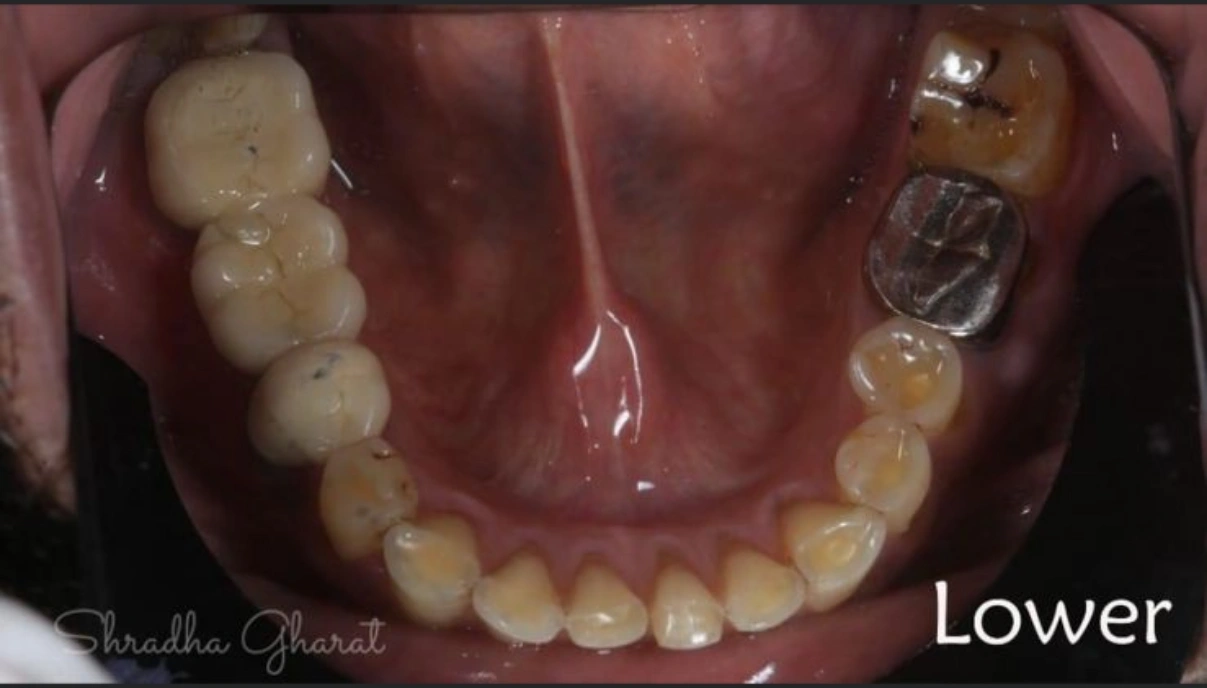

Full mouth rehabilitation includes restoration of lost tooth structure and bite. This technique sensitive procedure involves buildup of lost tooth enamel and dentin. Missing tooth can be replaced with Dental Implants or dental bridges. A Full mouth Reconstruction procedure is mainly indicated for patients with extreme tooth wear.

Multiple dental treatments join hands to give you something more than a mere smile makeover. Based on the case history of patient and nature of defects, the following can be advised:-